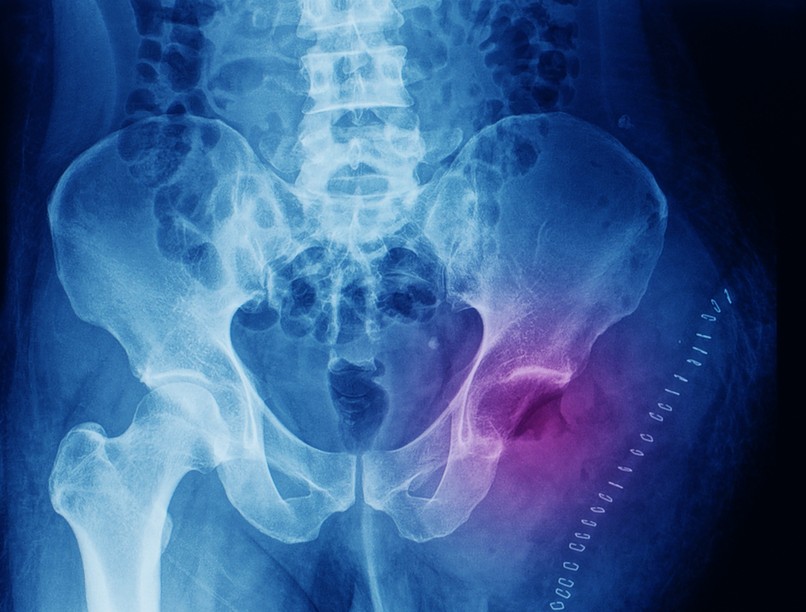

Röntgenvizsgálattal a következő látható. A jól differenciált, lassabban növő kondroszarkómára az jellemző általában, hogy centrálisan, vagyis csonton belül keletkeznek. A csontot felfúvó, lebenyes elváltozást hoznak létre.

A tumorban rendszerint eltérő mértékű mészlerakódások vannak. A csont felszínéről kiinduló kondroszarkóma a lágyrészek fele növekszik, későbbi stádiumban pedig már összefüggően, elmosódó képet ad. CT és MR képalkotó vizsgálat segít a lágyrész érintettség felderítésében és a műtét megtervezésében is. A biztos diagnózishoz szövettani mintavételt (biopsziát) kell végezni.